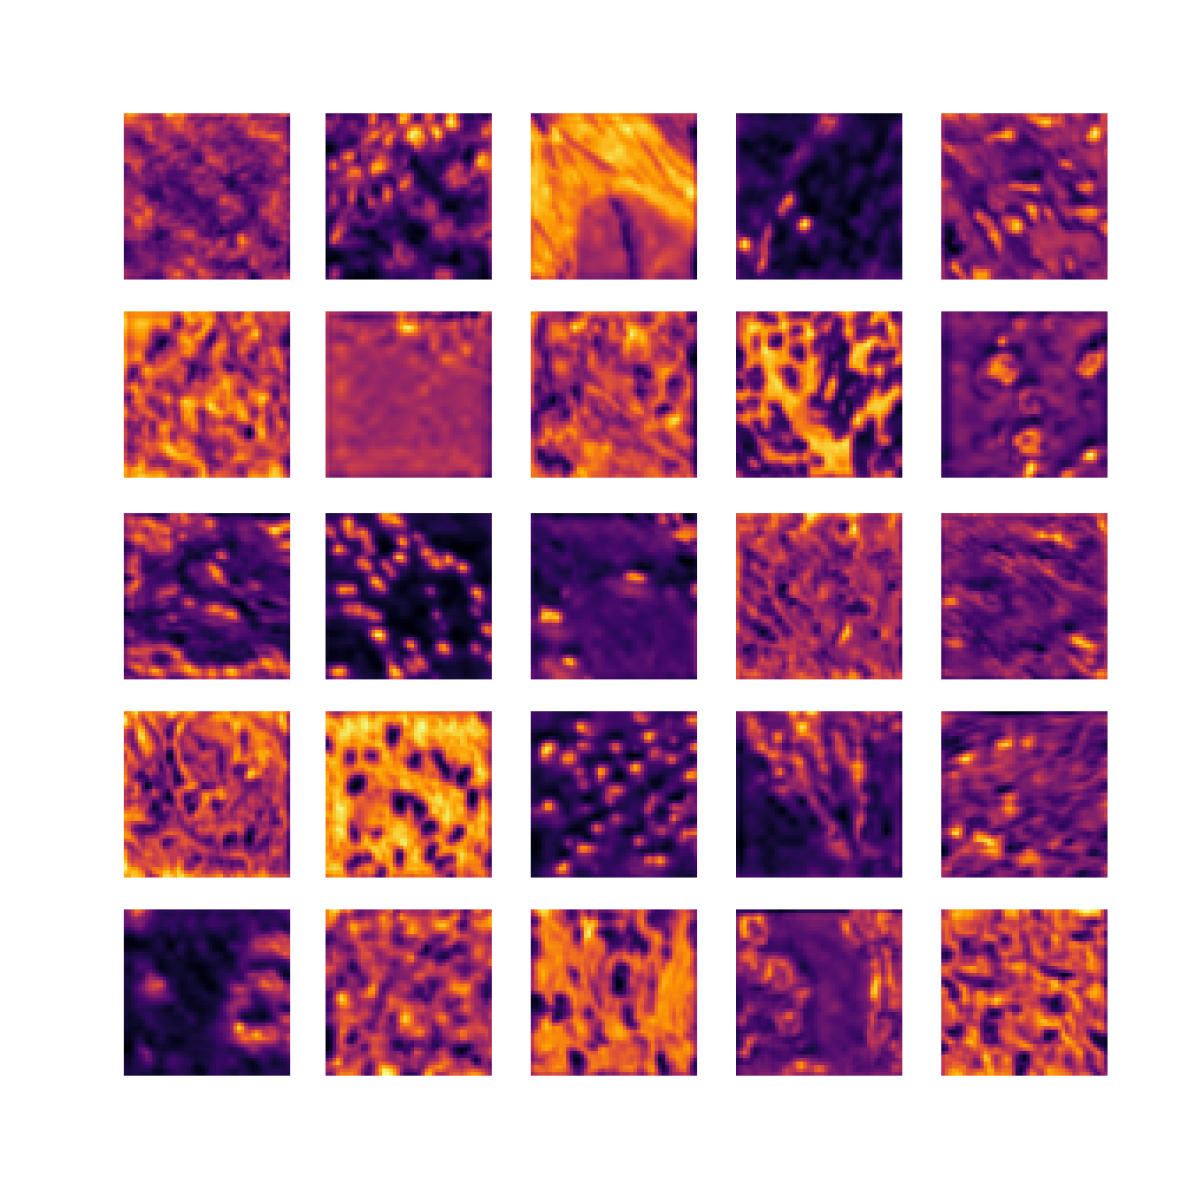

We also analyse the activation maps for each model using GradCAM as described in section S3. This offers more insight into the areas of the image which are contributing most heavily to the models’ representations. In Figure 4(b) we present some representative examples, however, a larger selection which was chosen at random is presented in Figures S10 to S25. The larger selection makes it easier to see the emergent patterns, including that privileged Siamese models tend to mainly identify features which are strongly present in both inputs, while unprivileged Siamese models tend to learn more diffuse features that are not specific to one cell phenotype or image region. TriDeNT ♆ incorporates both sets of features, learning both features specific to the privileged data and more the general features associated with unprivileged Siamese networks.

We can see in Figure 4(b) panel A that for ERG, the privileged Siamese model focuses almost exclusively on any nuclei which could be endothelial cells. As there are very few endothelial cells in the dataset, it could be an effective strategy to identify anything that could potentially be an endothelial cell to minimise the difference between the representations of the H&E model and the IF mask model. In the corresponding unprivileged Siamese image, we see that the model identifies some of these nuclei, albeit less strongly, but also focuses heavily on the other tissue and even the background, while strongly fixating on two spots of debris in the center of the image. This model has less ‘incentive’ to learn the weak features related to endothelial cells as these occur rarely and are not easy to detect, while more generic strong features such as the presence of connective tissue and the prevalence of background are more common and predictable from augmented images. We see that TriDeNT ♆ combines these two feature sets, strongly identifying nuclei while also identifying the connective tissue.

In panel C we see a similar pattern, with the privileged Siamese model fixating solely on the nuclei, while the TriDeNT ♆ model takes a more balanced approach. The unprivileged Siamese model appears to focus on a single cluster of nuclei while neglecting others, and similarly identifies an area of fibroblasts with its distinctive pattern but does not others.

In contrast to panels A and C which represent models with poor privileged Siamese results, panels B and D represent models whose privileged Siamese results were comparable to both TriDeNT ♆ and even the supervised baseline. It is therefore interesting to note that there are far more similarities between the privileged Siamese and TriDeNT ♆ models in both cases. Particularly in panel B, TriDeNT ♆ and the privileged Siamese model return virtually identical heatmaps, with both strongly identifying epithelial nuclei and neglecting the same areas of connective tissue. The unprivileged model in this case appears to focus solely on the centre of the image, giving a significantly different heatmap to the other panels.

Panel D again shows the previous pattern, with the privileged Siamese model identifying the features strongly present in the privileged data – fibroblasts – while neglecting the nuclei present. TriDeNT ♆ also strongly identifies the connective tissue, but, unlike the privileged Siamese model, does not completely neglect the nuclei. The unprivileged Siamese model primarily identifies background, and does not appear to identify the nuclei in this example.